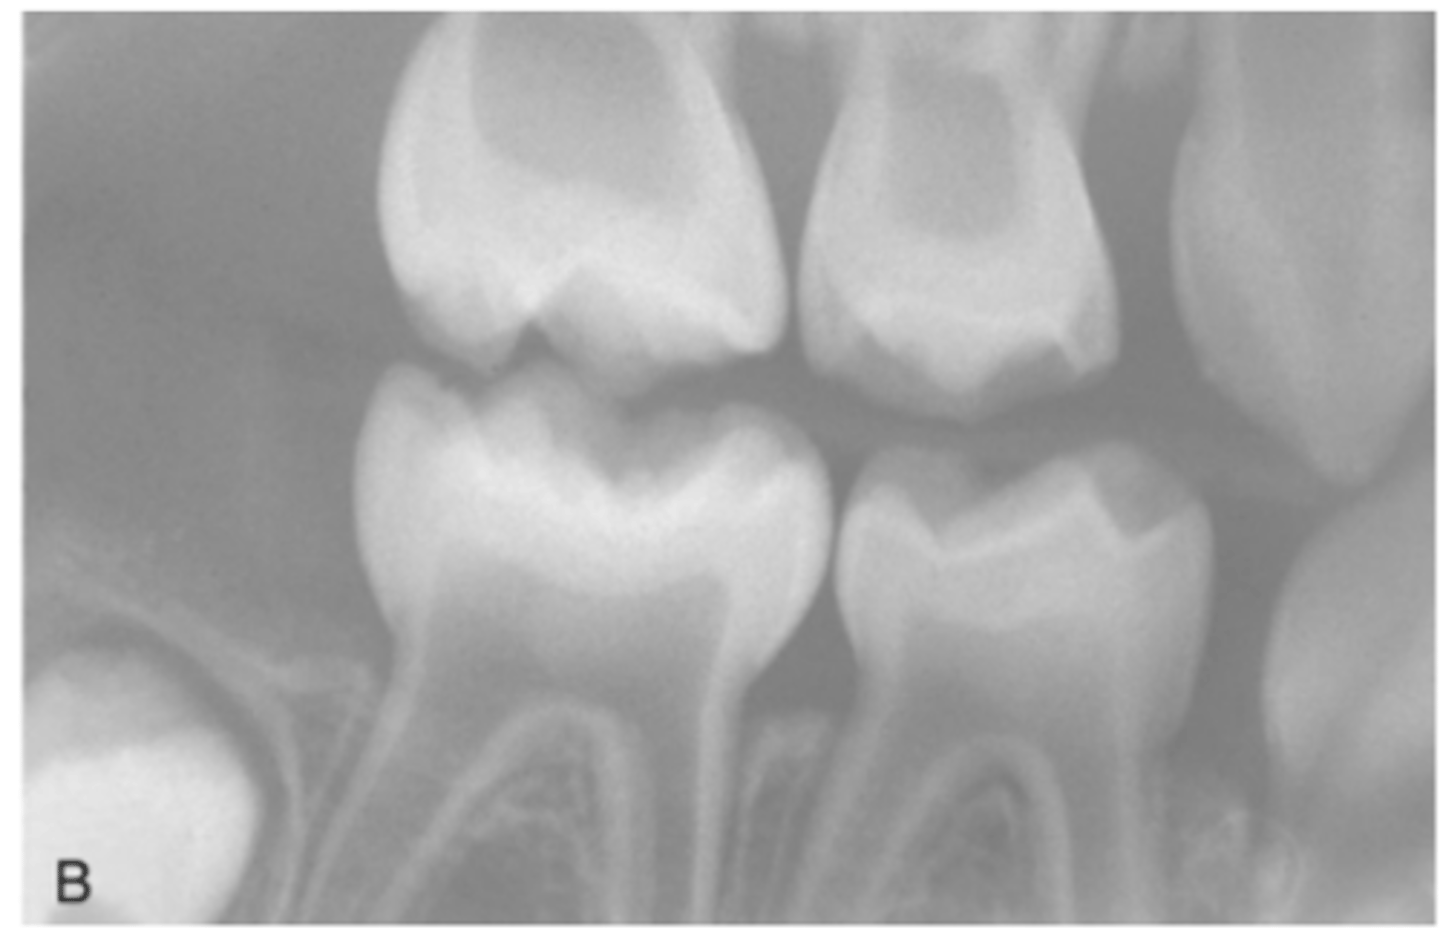

What are some radiographic signs seen in Osteogenesis Imperfecta

Wider pulp chamber

What do dentinal defects in Osteogenesis Imperfecta lead to?

Attrition, loss of vertical dimension, and potential tooth loss.